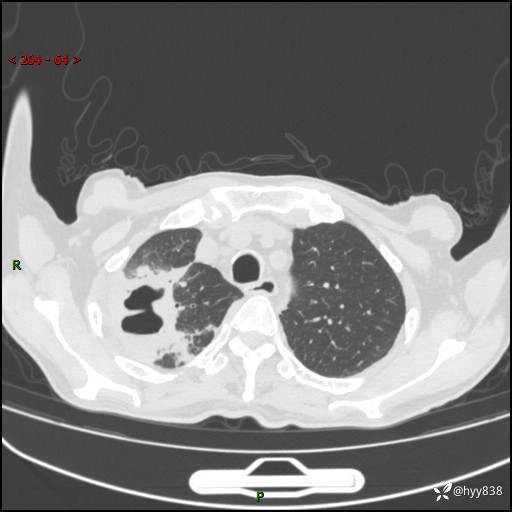

一个月后第二次CT检查(常规抗感染,患者不配合:增强、住院---)